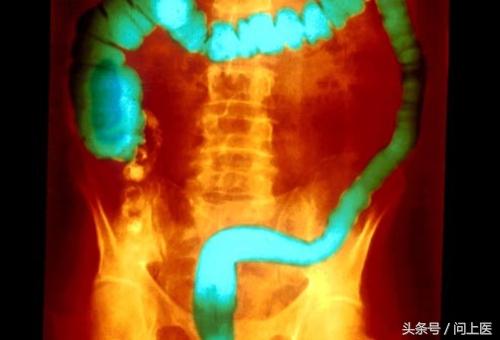

2 / 24 溃疡性结肠炎预警:腹痛

腹痛和血性腹泻可能是溃疡性结肠炎的迹象,这些症状的严重程度从偶尔轻度发生到持续重度发生。上图是一部分发生溃疡性结肠炎典型变化的大肠。